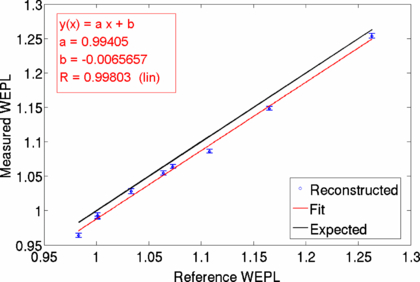

Figure 10 shows the resulting reconstructed WEPL image of the cylindrical PMMA head phantom (a) and the known insert WEPL values (Jäkelet al 2001) in known phantom geometry (b). The overall reconstructed phantom shape with the inserts is in excellent agreement with the given geometry. Due to the reconstruction with a limited number of angles, streaking artifacts can be seen. To some extent image quality could be improved by filtering of raw image data. The quantitatively measured WEPL values were analyzed by averaging the WEPL values of the tissue equivalent inserts over an area of 1.6 cm in diameter. The measured WEPL values from the reconstructed image were plotted against the known WEPL values as shown in figure 11. The obtained data was linearly fitted (red) and shows in comparison to the expected values (black line) a systematic shift in WEPL of −0.007. The measured WEPL values seem to be lower than the known WEPL values.

Standard imageFigure 11. The WEPL values of the tissue equivalent inserts have been evaluated by calculating the mean and the standard deviation of ROIs placed over the inserts in the WEPL image. The reconstructed WEPL values are plotted against the expected reference values and are linearly fitted with the figure of merit given by the Pearson's correlation coefficient R.

Download figure:

Standard imageThe Ram–Lak filter used in the back projection algorithm is designed to cut-off high frequencies above a set threshold. This filtering process can lead to decreased values in the position space. To account for this, scaling of the obtained data is necessary. In x-ray CT imaging this is performed by applying a linear transformation called Hounsfield scale. Here, for the reconstruction in carbon ion CT, a scaling factor was obtained by comparison of the measured WET values of a single projection with the WET values obtained from the reconstructed image. In figure 12(a) the measured WET distribution for one projection is compared to the calculation from the reconstructed image. Clearly the noise originating from the reconstruction process can be seen. The reconstructed image underestimates the measured values. By multiplication with an estimated correction factor, both distributions agree well. This correction factor was found to be valid for all measured projections and WET distributions. Applying this correction factor to the obtained reconstructed WEPL values (figure 12(b)), the reconstructed and expected WEPL values agree within one standard deviation.